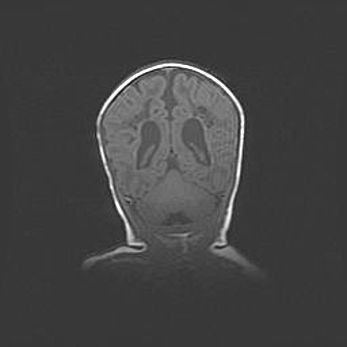

Мальформация Денди-Уокера. Киста задней черепной ямки.

Агенезия мозолистого тела.

Возраст: 2,5 месяца

Вес: 2420 г

Пол: женский

Окружность головы: 37 см

Срок гестации: 32 недели

Мальформация Денди—Уокера — редкий вид патологии ЦНС, представляющий собой врожденный порок развития каудального отдела ствола и червя мозжечка, ведущий к неполному раскрытию срединной (Мажанди) и латеральных (Лушка) апертур IV желудочка мозга. Для этогно синдрома характерна триада симптомов: гипотрофия червя мозжечка и/или полушарий мозжечка, кисты задней черепной ямки, гидроцефалия различной степени. В 70% случаев порок сочетается и с другими аномалиями головного мозга, в частности с агенезией мозолистого тела.